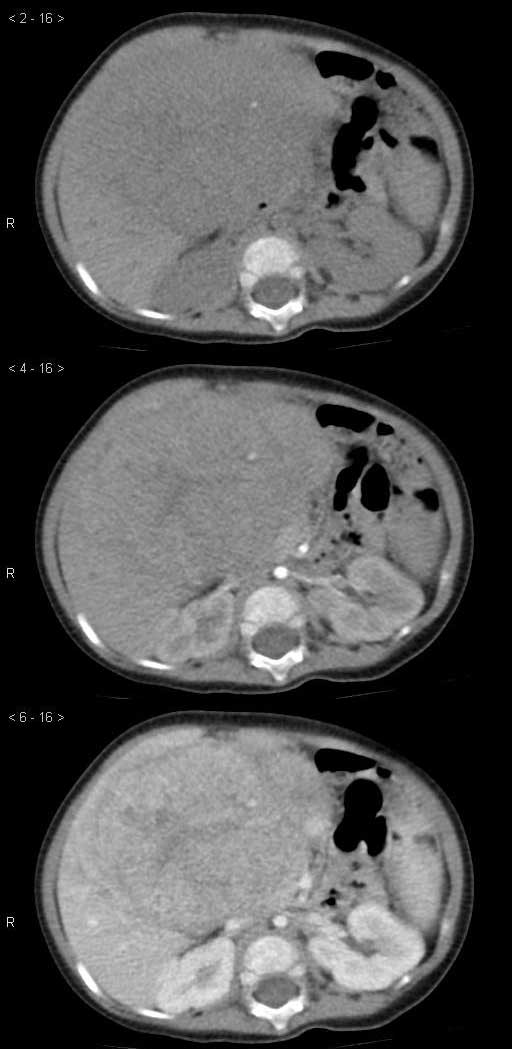

男孩,7个月,因呕吐1个月就诊,超声提示肝脏占位。

实验室检查:AFP明显升高。

诊断:肝母细胞瘤

肝内单发占位,50%病例有钙化灶,病变边界清楚,增强扫描不均匀强化,内部可见无强化坏死区。

肝右叶可见巨大低密度占位,边缘欠光整,动脉期,肿块周边结节强化,内见分隔及条片状低密度影,门脉期,分隔进一步强化,肿块密度低于肝实质,考虑肝母细胞瘤可能性大。